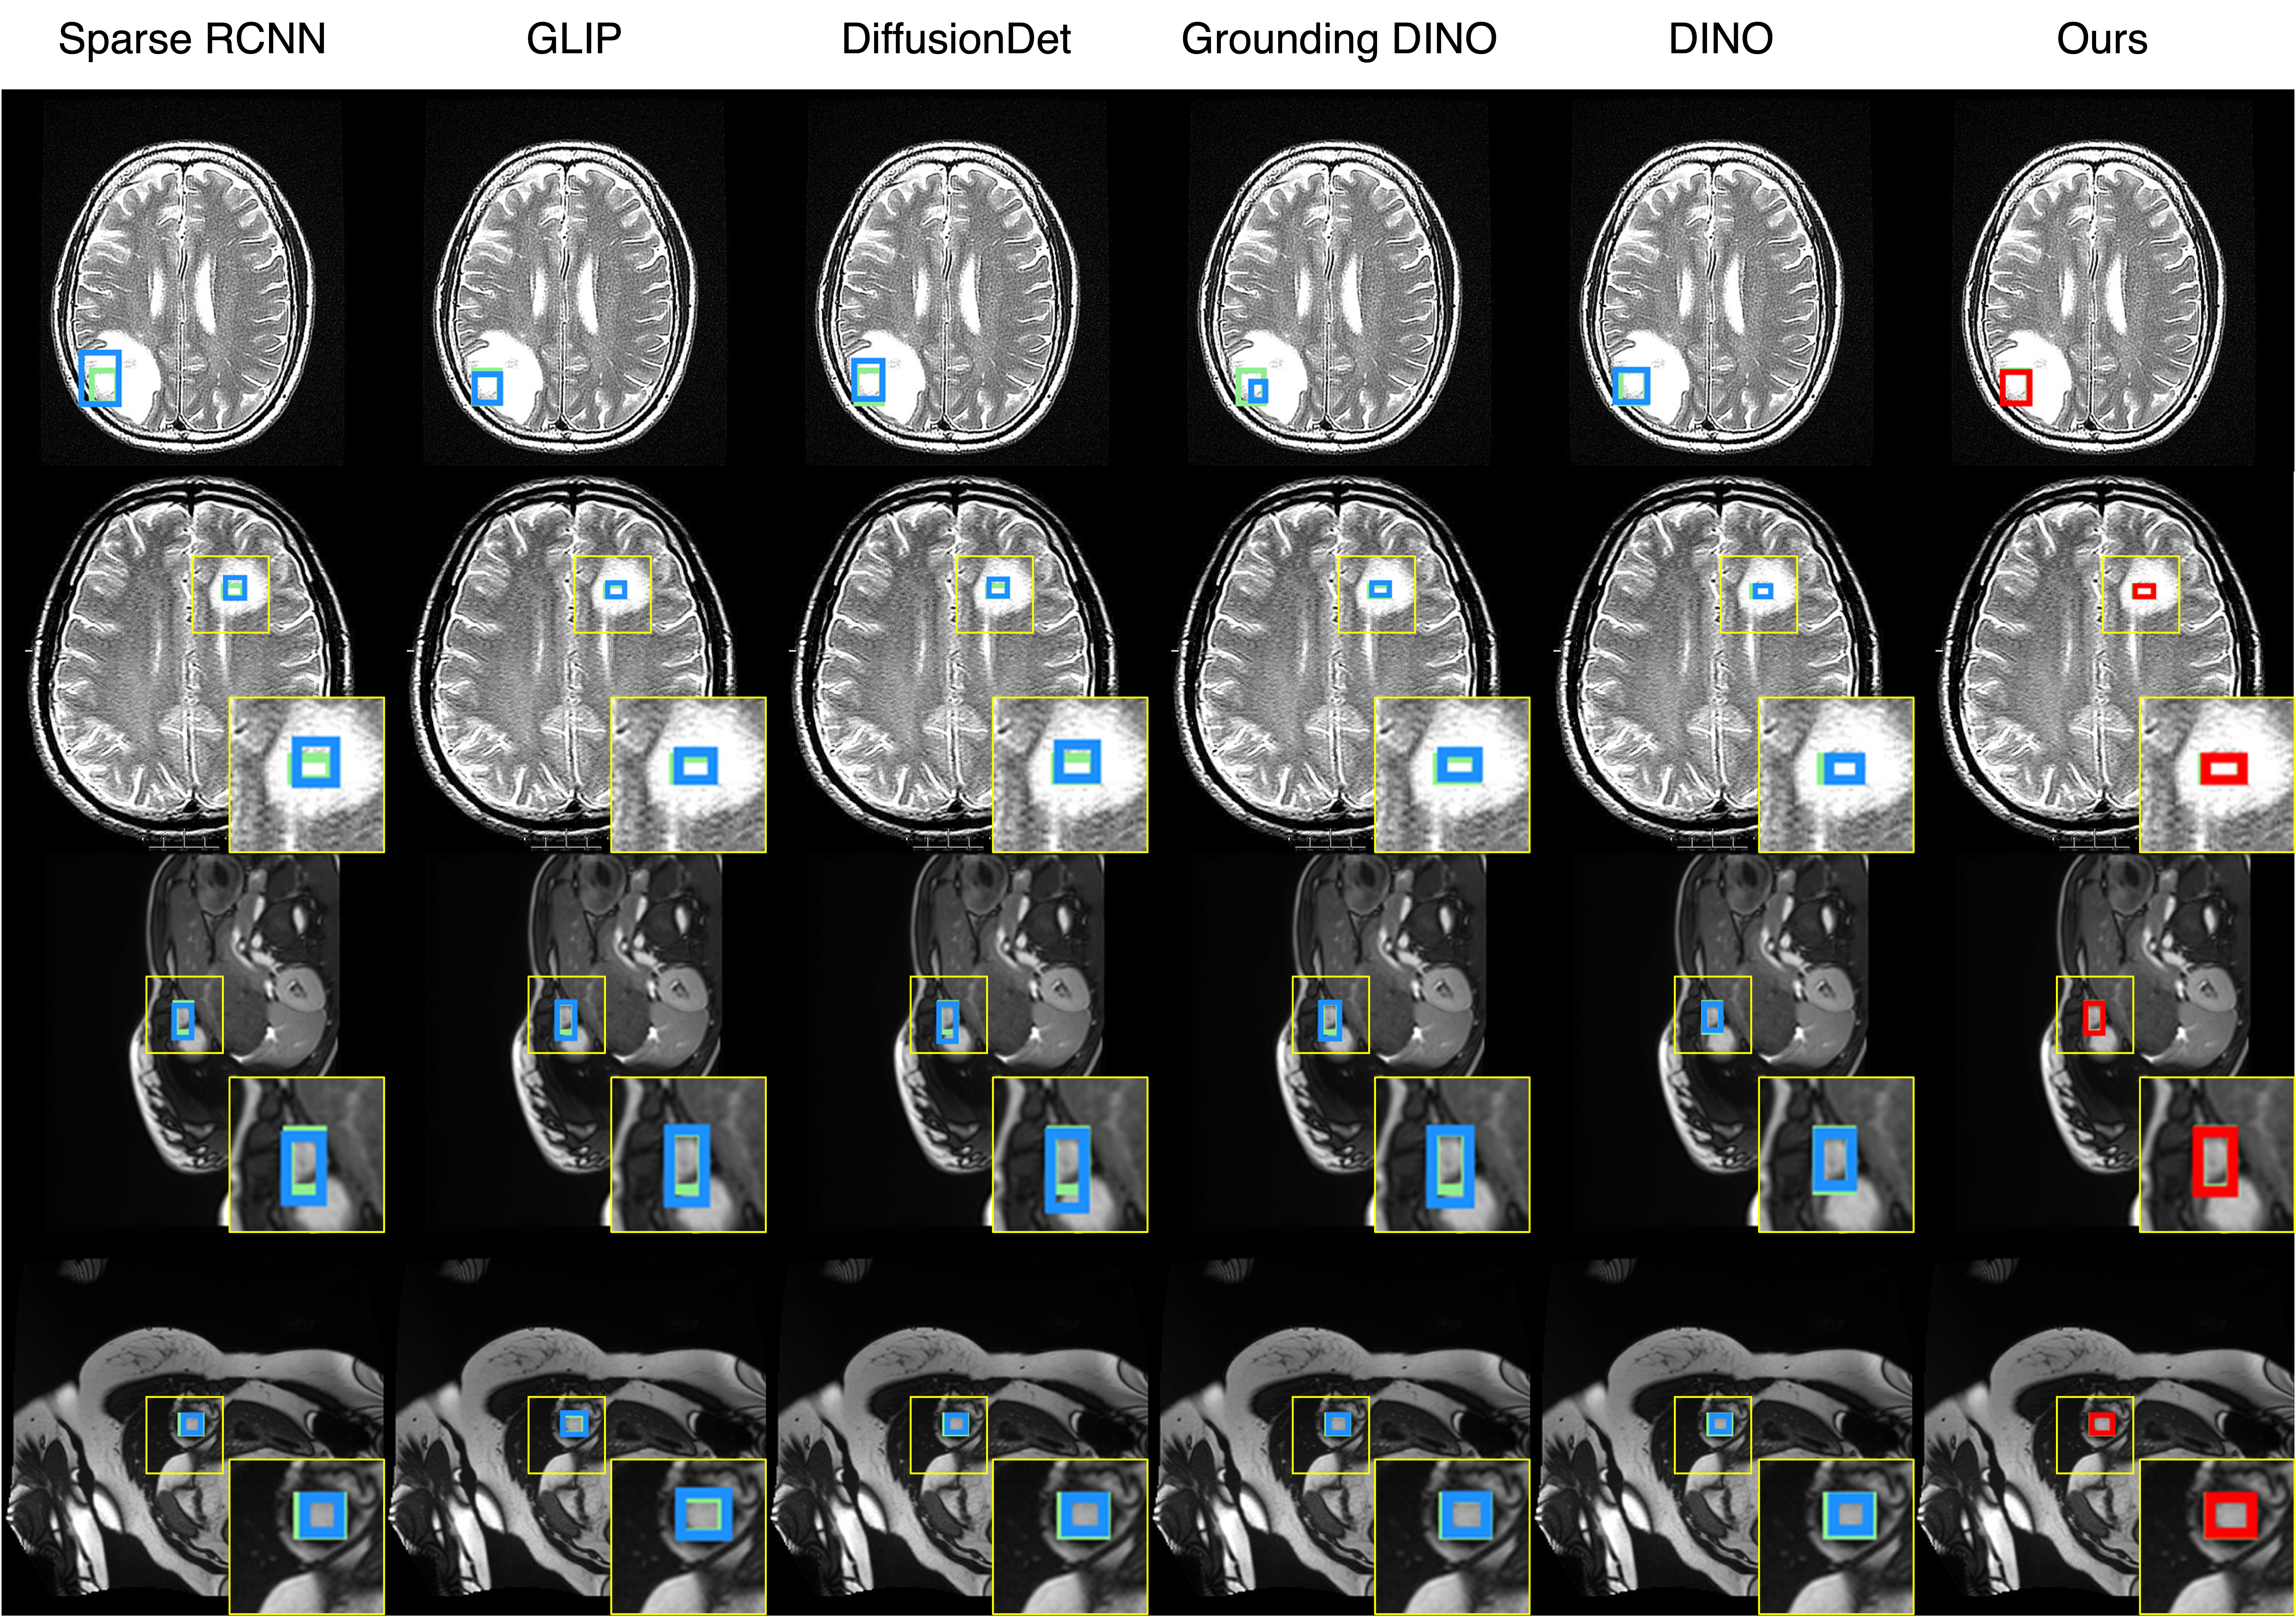

Qualitative comparison results

Qualitative Comparison. Comparison results between various state-of-the-art detection methods and the proposed method is shown above. Our method effectively leverages modality context to significantly enhance anomaly localization (red), compared to baseline results (blue). Ground truth bounding boxes are green. For cases where the bounding boxes are small, insets show an enlarged view of the highlighted yellow region.